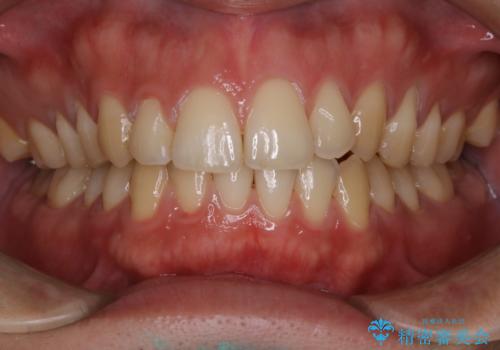

- マスクの着用により、以前より口臭が気になるとのことでした。しっかりと全体的なクリーニングを希望されたため、PMTC60分コースを行いました。

バイオフィルム(細菌の塊)を破壊し、歯の表面をツルツルにすることでお口の中の細菌数を減らし歯周病のリスクが定着するのを防ぎます。更に、歯に新しい汚れがつきにくい状態になります。

バイオフィルムが除去されると、ご自身本来の歯の表面になります。PMTCをすることで口臭予防にもなり、定期的に行うことが大切です。